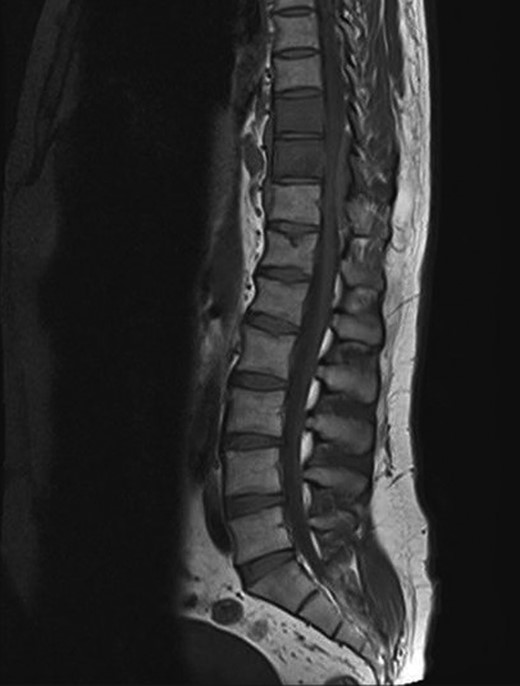

A 30-year-old male patient was admitted to our clinic with back pain. Pain was provoked by movements. The severity of pain was associated with the inability to perform the activities of daily living. The patient did not have any lymphoma-related B-type symptoms, including body weight loss, fever and sweat at night. He did not have a past and family history. There was no neurological deficit. Routine laboratory test results were normal. A magnetic resonance imaging (MRI) scan of the thoracic spine demonstrated an epidural tumor at the T9–11 level (Figs 1–3). The patient underwent spinal cord decompression via total laminectomy of T9–11 levels. Subtotal resection of the tumor was performed. Histological examination revealed the polymorphous cellular infiltration by histiocytes, large mononuclear cells and lacunar Reed–Sternberg cells with folded multi-lobed nuclei and small nucleoli (Fig. 4). Immunohistochemical staining was positive for CD15 and CD30 and negative for CD3, CD20, CD79a or CD45Ro. These features were most frequently observed in the mixed cellularity type of Hodgkin's lymphoma. Histological examination of the vertrebral body revealed no abnormality. The results of all other examinations (F-18 fluorodeoxyglucose positron emission tomography (F-18 FDG PET/CT), bone marrow biopsy and computed tomography (CT) of the chest, abdomen and pelvis) were negative for an occult disease. The patient was referred to the hematology department to undergo staged treatment. Six courses of chemotheraphy containing ABVD regimen (adriamycin, bleomycin, vinblastine and dacarbazine) were given to the patient. Postoperative MRI scan did not reveal any evidence of Hodgkin's disease (Fig. 5), F-18 FDG PET/CT, CT of the chest, abdomen and pelvis were obtained in 24 months and did not reveal any evidence of Hodgkin's disease.

Postoperative MRI scan did not reveal any evidence of Hodgkin's disease.

Moridaira et al. [4] reported a case of Hodgkin's disease at T8–10 epidural space. Rao et al. [6] published a case with primary spinal epidural Hodgkin's lymphoma. Our case is apparently the seventh case to be diagnosed with Hodgkin's disease who presented with spinal cord compression due to epidural space without lymphoma elsewhere. The abnormal MRI marrow signal of the T9 and T10 vertebral bodies can be seen in Fig. 5. Maybe the tumor in fact originated within the abnormal T9 or T10 bone marrow and spread to the epidural space via the epidural venous plexus. But histological examination of the vertebral body revealed no abnormality.